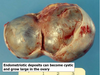

Q

Name 3 unusual sites of endometriosis

A